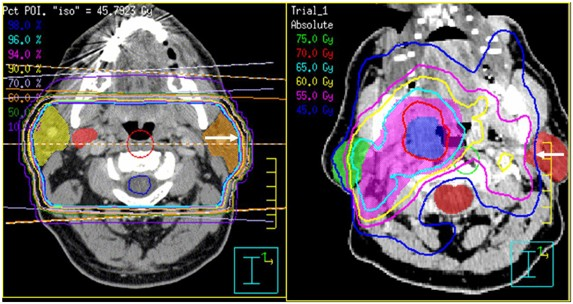

Data collection and analysis: Positional changes during treatment were tracked using cone-beam CT (CBCT). Shifts along the side-to-side (X), front-to-back (Y), and up-and-down (Z) directions were measured and summarized as mean ± standard deviation over all sessions. The decision to use either 3DCRT & IMRT was customized for each patient, taking into account the oncologist’s experience, expected benefits in dose distribution, anatomical considerations, and sometimes how urgently treatment needed to begin (Figure 1).

Figure 1 Intensity modulated radiotherapy planning of head and neck cancer.